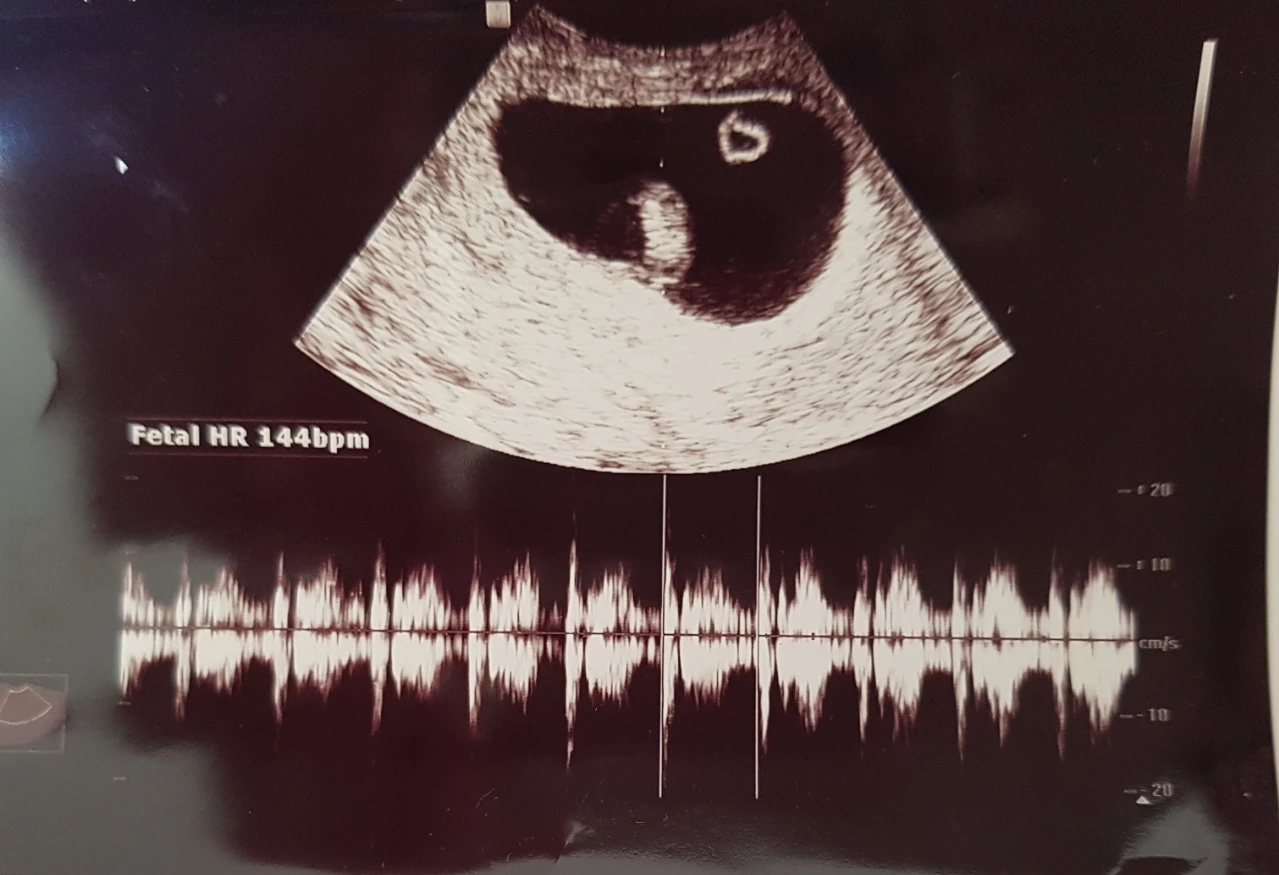

<미술상담치료의 종료 : 둘째의 임신>

둘째가 생기게 되었기 때문이었다. 치료 상담 선생님께서는 굉장히 기뻐해 주셨다. 아이가 생긴 것만큼 마음이 안정된 증거는 없다고 하시며 진심으로 축하해주셨다.